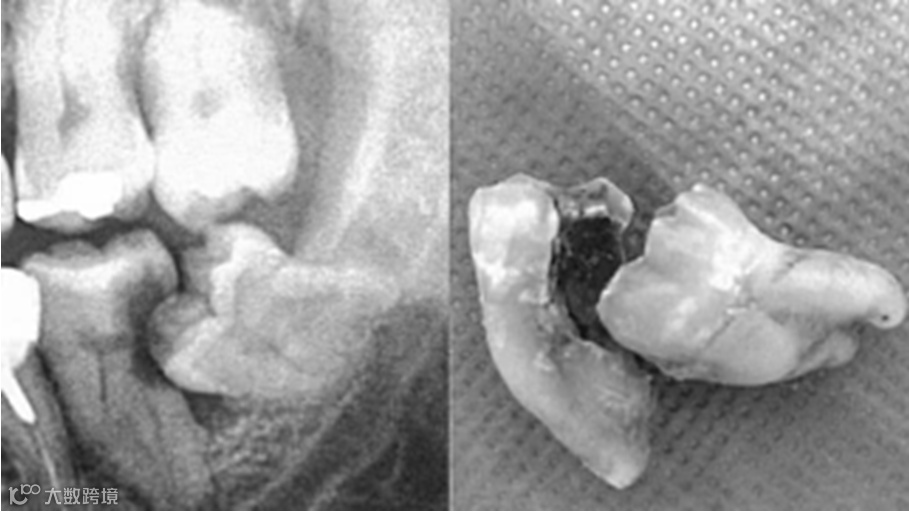

2、龋齿。

位置不正的智齿与第二磨牙之间容易积存食物残渣,而且不易清洁,一般数月可形成龋齿,直接破坏牙体组织。

4、引起第二磨牙远中牙根的吸收。

如果智齿完全埋伏在颌骨当中,它还在不断萌出,就可以压迫第二磨牙远中的牙根,引起牙根吸收。